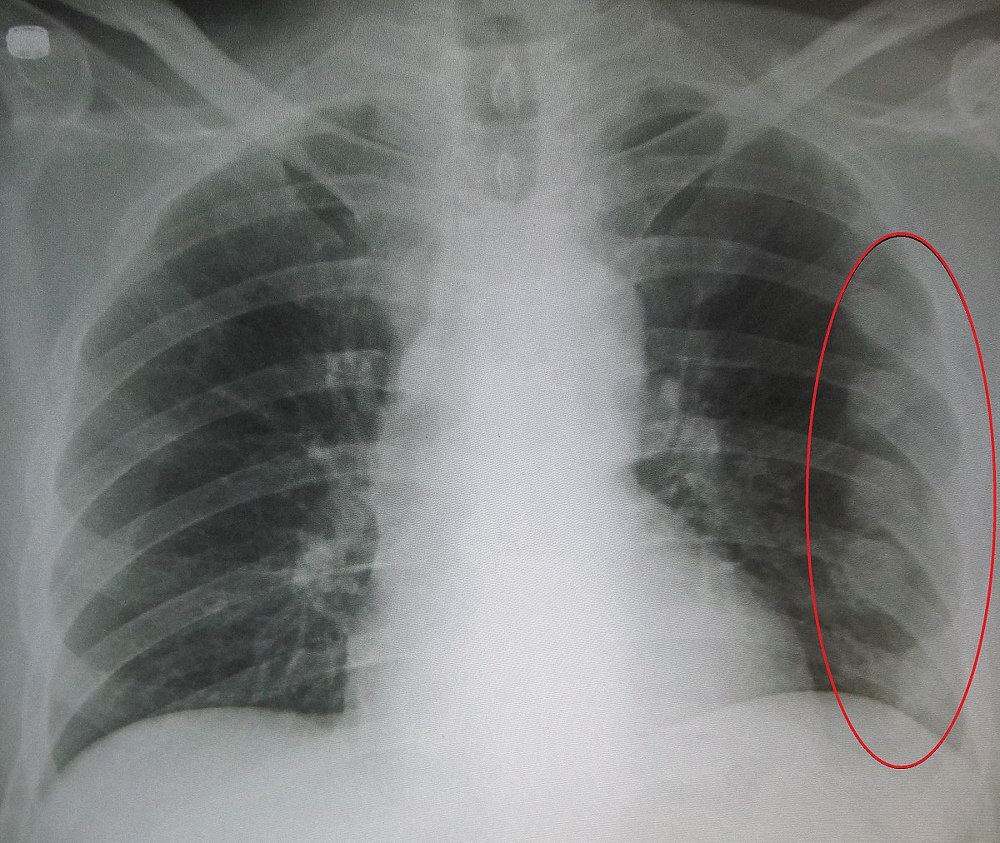

갈비뼈가 금갔을 때뿐만 아니라 모든 골절 사고는 반드시 의사의 진단을 받아야 합니다. 상황에 따라서는 X-레이 검사나 CT 스캔이 필요할 수도 있고, 경우에 따라서는 수술이 필요할 수도 있습니다. 따라서 위에서 언급한 대처방법은 임시 조치일 뿐, 전문가의 의견을 듣는 것이 가장 안전합니다.